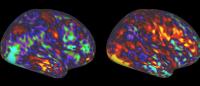

The new brain imaging study shows that parts of the TPJ—involved in the understanding of complex social scenes—are less active in people with schizophrenia. (Image: Patel laboratory)

In the brain, the difference was linked to a part of the brain called the temporoparietal junction. The area lit up in brain scans when people scanned social scenes (like those depicted in “The Good, the Bad, and the Ugly”) for the social information needed to understand the scene.

“That this area is inactive in people with schizophrenia was really striking,” Patel says. “Based on this data and our model, we think this area of the brain is part of a circuit that tells us where to look for social cues and also routes the incoming information to higher-level areas of the brain for interpretation.”